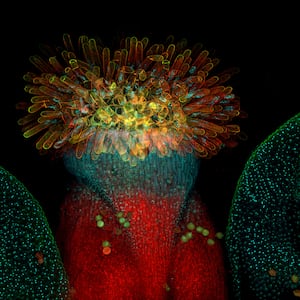

In the study, researchers gene-edited mice to mimic the mutations that one would find in humans with Robinow syndrome. Embryos with FZD2 mutations had cleft palates and shortened limbs in comparison to unedited mouse embryos.

But the key innovation of the study came when the researchers realized that FZD2 affects a key developmental pathway. The mutations in the mice set off a cascade of developmental irregularities that gave the mice their characteristic Robinow-like symptoms. The researchers reasoned that even if they couldn’t fix the FZD2 gene, they could prevent the cascade from happening by introducing a small-molecule drug to a developing mouse embryo during its mother’s pregnancy.

And their efforts worked: Mice with the mutation had significantly longer limbs when treated with the drug compared to embryonic mice that went untreated. Don’t start sizing up your wardrobe yet, though.It’s unclear whether this drug would be as effective in humans, or what the effects might be of using it without a mutation in this key developmental pathway.